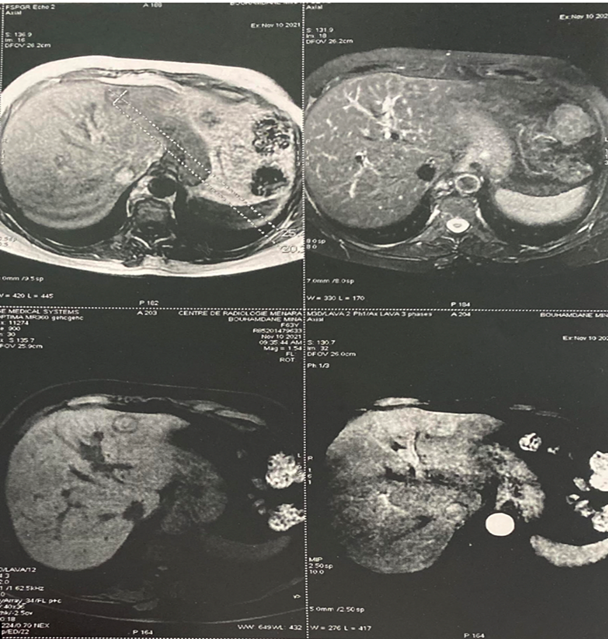

Epithelioid Hemangioendothelioma a Rare Entity Cause of Chronic Abdominal Pain: Case Report

Aouroud Hala, Aouroud Meryem, Adil Ait Errami, Sofia Oubaha, Zouhour Samlani, Khadija Krati

International Journal of Innovative Research in Medical Science·September 6, 2022